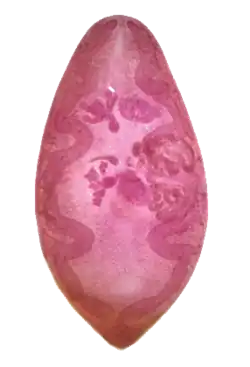

| An adult specimen stained with carmine | |

In size, shape, and color, Paragonimus westermani resembles a coffee bean when alive. Adult worms are 7.5 mm to 12 mm long and 4 mm to 6 mm wide. The thickness ranges from 3.5 mm to 5 mm. The skin of the worm (tegument) is thickly covered with scalelike spines. The oral and ventral suckers are similar in size, with the latter placed slightly pre-equatorially. The excretory bladder extends from the posterior end to the pharynx. The lobed testes are adjacent from each other located at the posterior end, and the lobed ovaries are off-centered near the center of the worm (slightly postacetabular). The uterus is located in a tight coil to the right of the acetabulum, which is connected to the vas deferens. The vitelline glands, which produce the yolk for the eggs, are widespread in the lateral field from the pharynx to the posterior end. Inspection of the tegumental spines and shape of the metacercariae may distinguish between the 30-odd species of Paragonimus spp. but the distinction is sufficiently difficult to justify suspicion that many of the described species are synonyms.[5]

- Adults: Adult flukes are typically reddish-brown and ovoid, measuring 7 to 16 mm by 4 to 8 mm, similar in size and appearance to a coffee bean. They are hermaphroditic, with a lobed ovary located anterior to two branching testes. Like all members of the Trematoda, they possess oral and ventral suckers.